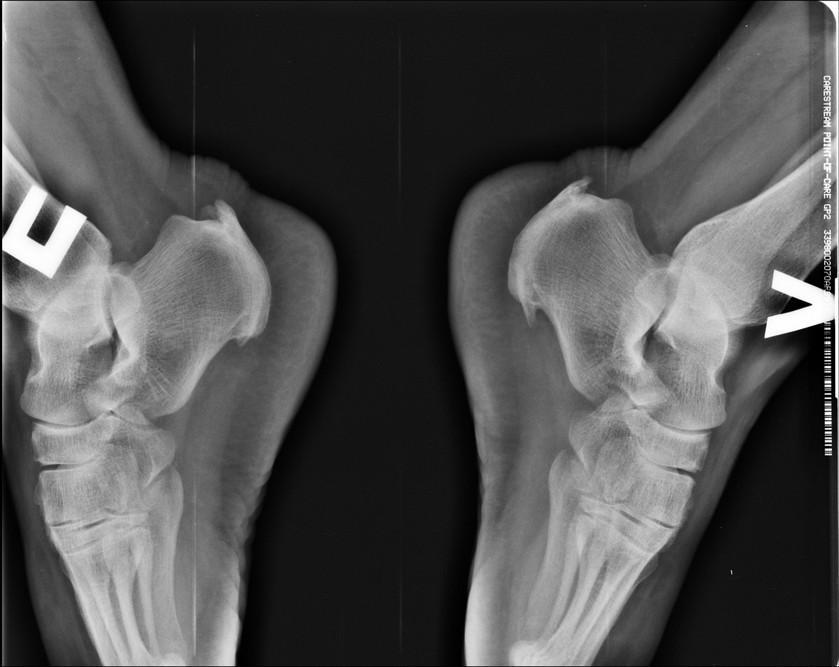

[Ortho] Инсерционный тендинит ахиллова сухожилия

Здравствуйте, коллеги. Пациетка 37 лет, давность заболевания 3 года.

Консервативное лечение без эффекта (иммобилизация, НПВС, местное и

физиолечение). Сопутствующее ожирение 3 степени. Снимки прилагаю. МРТ

нет. Внешне классическая картина опухолевидных плотных болезненных

образований в области прикрепления ахилла. Пунктировал, жидкости не

получил. Видимо пора ставить вопрос оперативного лечения, хотел бы

услышать ваше мнение, особенно тех, у кого есть такой опыт. Доступ

открытый. Спасибо.